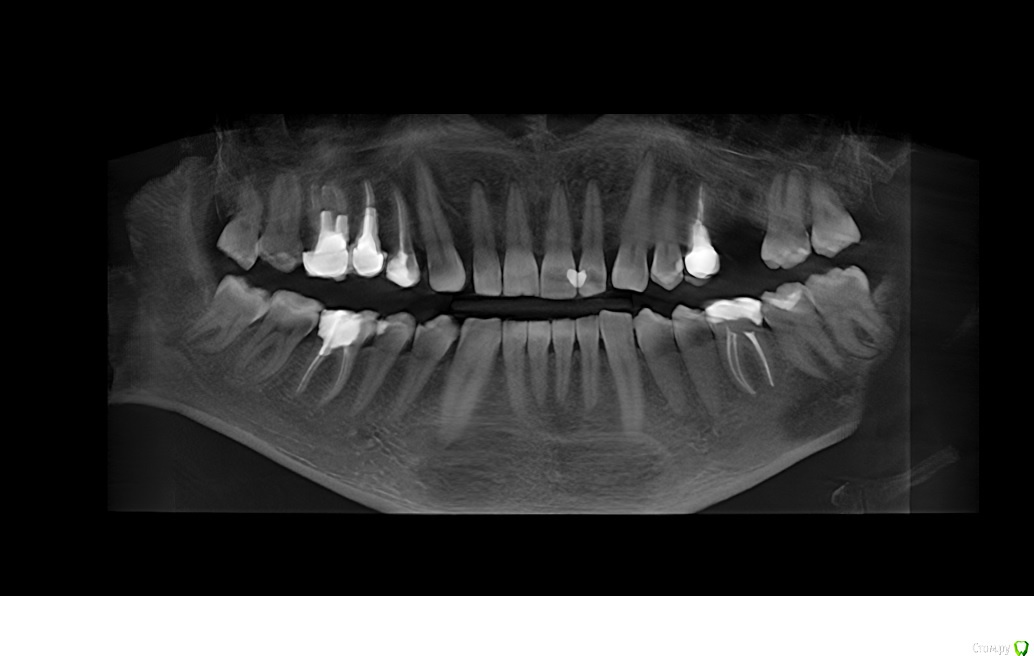

Vania777 Опубликовано 14 сентября, 2020 Поделиться Опубликовано 14 сентября, 2020 (изменено) так как есть кариозная полость ( опираясь на данные снимка) с правого бока, возможно придется вскрывать каналы и возможно удалять нерв ( от 7 до 20 тыс цена вопроса ) , с виду зуб абсолютно здоровый и не болит, просто хочу установить имплант на соседнее место взамен удаленного зуба и сказали обязательно лечить соседний зуб (тот что слева на фото) , действительно ли такой объем работы нужно делать, с удалением нерва ? Изменено 14 сентября, 2020 пользователем Vania777 Ссылка на комментарий

red_butler Опубликовано 14 сентября, 2020 Поделиться Опубликовано 14 сентября, 2020 так как есть кариозная полость ( опираясь на данные снимка) с правого бока, возможно придется вскрывать каналы и возможно удалять нерв ( от 7 до 20 тыс цена вопроса ) , с виду зуб абсолютно здоровый и не болит, просто хочу установить имплант на соседнее место взамен удаленного зуба и сказали обязательно лечить соседний зуб (тот что слева на фото) , действительно ли такой объем работы нужно делать, с удалением нерва ? снимок не информативен Ссылка на комментарий

red_butler Опубликовано 15 сентября, 2020 Поделиться Опубликовано 15 сентября, 2020 снимок не информативен то что Вы показываете, является панорамной реконструкцией компьютерной томограммы, этот снимок не информативен. Нужны или срезы Кт зоны интереса, или вся Кт (но ее не все доктора смогут или захотят скачать) Ссылка на комментарий